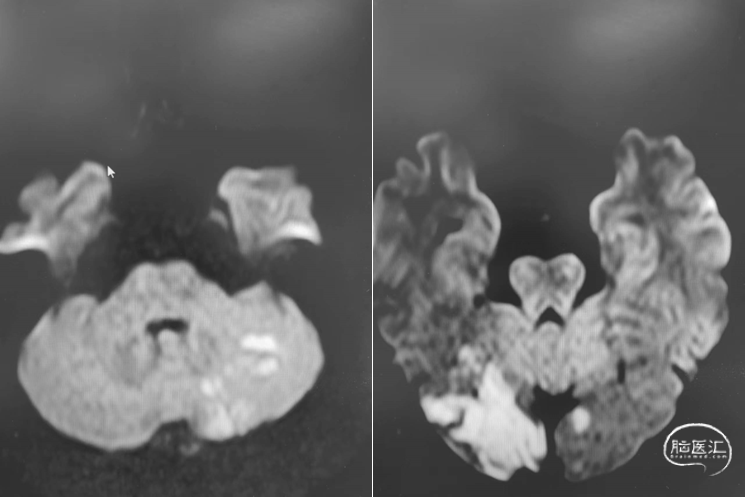

首次发病:

DWI

MRA

重要影像结论:后循环供血区多发梗死灶,后循环血管显影不良。